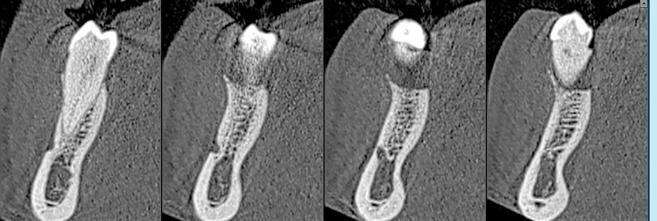

Prima dell’estrazione (S0), ad ogni paziente è stata eseguita una scansione intraorale tramite scanner iTero (Align Technology) (Fig. 2), e le scansioni sono state archiviate. A distanza di 2 mesi dall’estrazione è stato creato un lembo vestibolare a busta, a mezzo spessore, è stato inserito l’impianto nel sito (Figg. 3, 4) ed è stata posizionata la matrice in collagene suino volumetricamente stabile Geistlich Fibro-Gide (Geistlich Pharma), stabilizzandola al periostio con due punti di sutura riassorbibili interni (Fig. 5)7. Il lembo è stato quindi suturato con suture non riassorbibili e punti sospesi in modo da garantire la chiusura primaria e mantenere la matrice sommersa ma non compressa (Fig. 6).